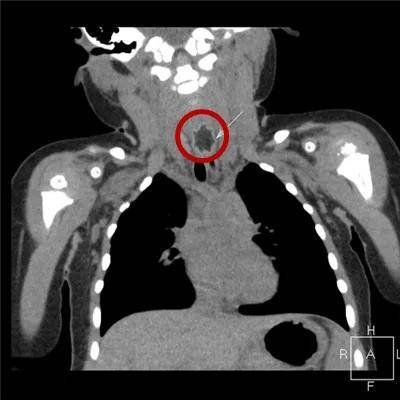

2岁·电池

纽扣电池塞入鼻腔一天。幸好电池停留在了鼻腔,没有进入肺部或胃里。

如果电池在胃中被胃酸腐蚀后会崩解,进而流出腐蚀性液体,腐蚀性的液体有可能造成孩子的终身残疾。